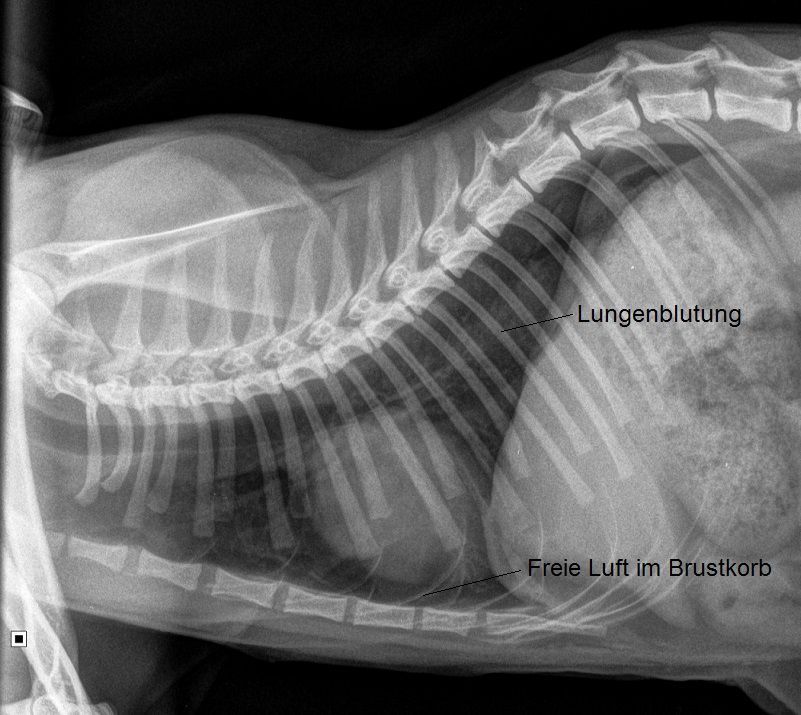

Ada ist apathisch und kann in der Hinterhand nur schlecht stehen, das linke Hinterbein wird komplett entlastet. Im Zuge der Abklärung wird eine Schienbeinfraktur links sowie Beckenfrakturen, Lungenblutungen und ein Lungenriss diagnostiziert.

Ada sollte aufgrund ihrer wohl durch einen Autounfall bedingten Verletzungen umfassend betreut werden: Mit einer intravenösen Infusion muss der Schock bekämpft werden, das Tier müsste auseichend Schmerzmittel erhalten, und nach Abheilung der Lungenverletzungen sollte zumindest der Schienbeinbruch (und idealerweise auch die Beckenfraktur) chirurgisch versorgt werden.

Die Verletzungen von Ada sind allesamt nicht tödlich. In der Regel verheilen Lungenrisse und -blutungen nach einigen Tagen vollständig. Obwohl die Beckenfraktur idealerweise chirurgisch behandelt würde, ist eine konservative Behandlung (Ruhigstellung) bei dieser jungen Katze mit ihrer schnellen Knochenheilung durchaus eine erfolgsversprechende Lösung. Allerdings sollte die Schienbeinfraktur chirurgisch therapiert werden, da eine konservative Behandlung mittels Verbänden wenig erfolgsversprechend ist.